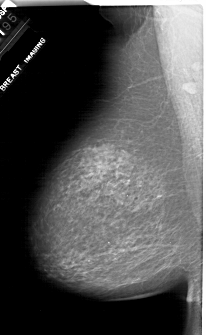

A_1917_1.LEFT_CC

LEFT_CC LINES 6871 PIXELS_PER_LINE 4051 BITS_PER_PIXEL 12 RESOLUTION 43.5 NON_OVERLAY